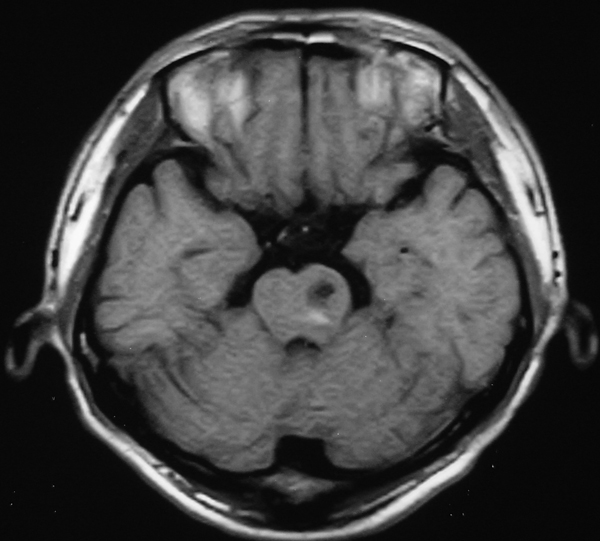

男 49岁 脑干腔隙梗塞5年。

这患者脑干(脑桥)腔隙脑梗塞是肯定的 有20002年资料 明天上传全部资料(当时工作忙 来不及)

图片质量不是很好!脑干偏左侧隐约可见低密度病灶,不知5年前怎样?单存本例支持:脑干梗塞!

1 单纯此图像定脑干梗塞依据不足. 2 可薄扫或核磁检查.

楼主是想具体分清是发生于脑桥还是中脑吧,脑桥的主要特征是结构就是小脑脚及四脑室,可以看到小脑脚及四脑室时就肯定是脑桥,中脑的主要特征就是环池,有完整的环池就是中脑,并且由于中脑短,一般只有一层可见,最多出现两层,本例层面应该是属于中脑层面,其上方应该是四叠体池及丘脑下部了.

楼主是想具体分清是发生于脑桥还是中脑吧,脑桥的主要特征是结构就是小脑脚及四脑室,可以看到小脑脚及四脑室时就肯定是脑桥,中脑的主要特征就是环池,有完整的环池就是中脑,并且由于中脑短,一般只有一层可见,最多出现两层。

不知小脑脚交叉到底另何指?中脑的病灶,应该和中脑导水管加以区别。

脑干梗塞在ct上是斑点状低密度,一般只能在桥脑或中脑才能显示,延髓是很难发现(伪影多)。mr上脑干梗塞应该是长t1长t2的斑点状表现。弥散能够发现早期梗塞灶,表现高信号。

①四脑室,脑桥平面有四脑室,中脑没有;

②环池:中脑平面有完整的环池,即前有脚间池、后有四叠体池。这是标准的om线扫描图像,如果不按om线扫描就有所变化;而桥脑没有完整环池,它前方是桥前池。

③三脑室,只要扫描基线偏移不大,看到三脑室出来同层面应该是中脑